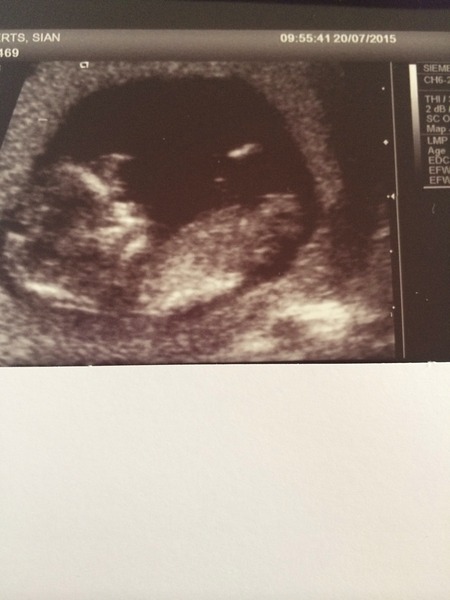

My scan was gorgeous. I saw a little wriggler with a good strong heartbeat. The measurements put me at exactly my dates so I'm a very happy bunny today.

And jelly congrats to you too! What a sweet scan pic.

Fab news jelly. Great picture!

What a fab pic jelly and excellent news on your scan too rally- I love seeing happy scan news!

Brummiegirl15 · 20/07/2015 14:39

More happy scan news!!

Am measuring slightly ahead and bang on 12 weeks today so due 1st Feb.

Am very very happy to see little one wriggling about

Congrats on all other good scans today!!

brummie Grin I've had a little cry at that scan, so happy for you!

Brummie and OhJelly gorgeous!! So happy for you both Smile

Lovely scan photos ladies Smile

Great photo Brummie, congratulations Smile